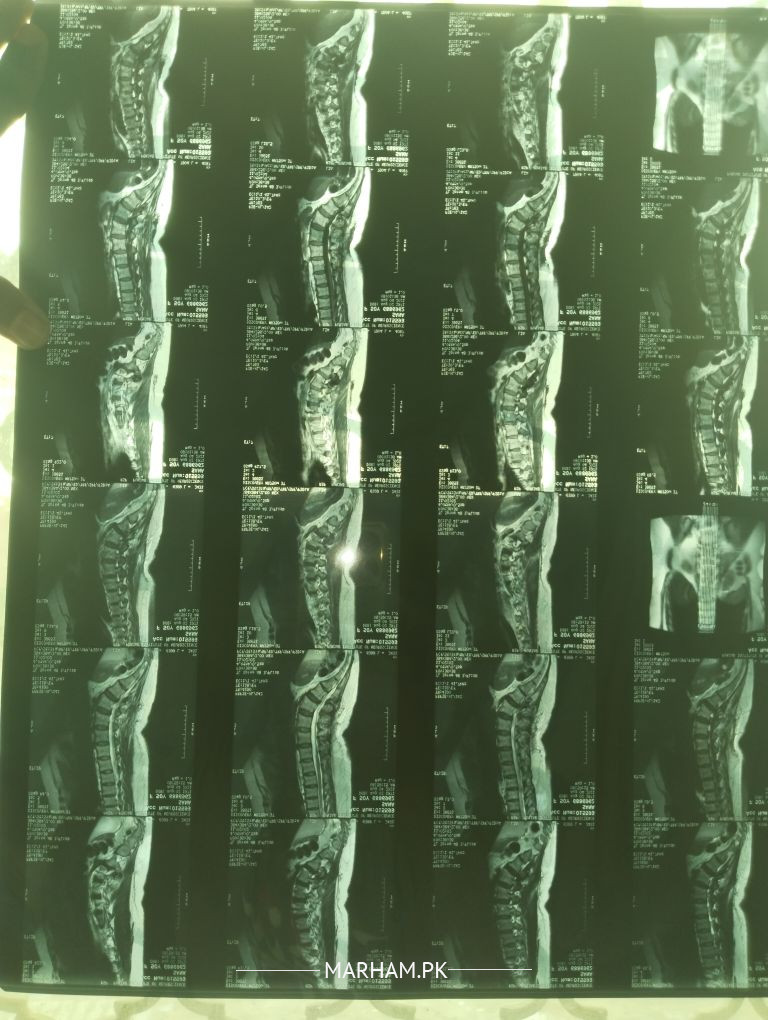

AoA doctors my mother is 53 years old she is a diabetes patient since 25 years.. doctor ny btaya tha k discs press hoye hen kindly see the exras related to this problem